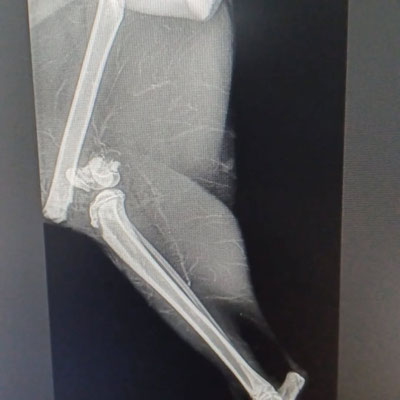

Katze mit Knochenbrüchen nach Sturz vom Balkon - September 2025

Die fünf Monate alte Selene ist von einem hohen Balkon gestürzt und hat sich beide Oberschenkelknochen sowie die Hüfte gebrochen. ABER sie will leben – und wir wollen sie auf

ihrem Weg unterstützen. Ihre Familie unternimmt leider keinerlei Anstrengungen, um Geld für sie zu sammeln, und hat sie aufgegeben.

Die Operation ist gut verlaufen. Ein Bein war in drei Teile gebrochen, das andere in elf. Letzteres wird höchstwahrscheinlich ihre Gehfähigkeit beeinträchtigen.